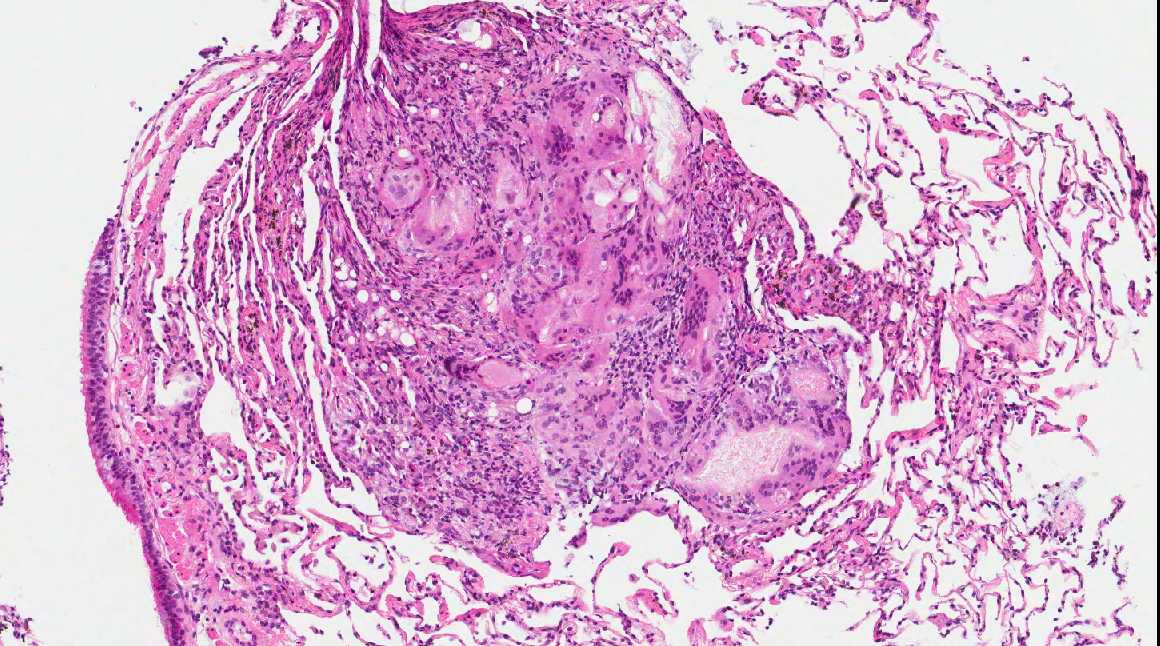

From www.pathologyoutlines.com

Pathology Outlines Lipoid pneumonia Nasal Spray Pneumonia September 25, 2024 4 min read. Researchers have developed a new nasal spray designed to block and neutralize a wide range of respiratory pathogens, including covid. This study explored lay people’s. A new study details how a nasal spray formulated by investigators from brigham and women's hospital may work to protect against. Nasal sprays could be a promising approach to. Nasal Spray Pneumonia.

Pathology Outlines Lipoid pneumonia Nasal Spray Pneumonia A new study details how a nasal spray formulated by investigators from brigham and women's hospital may work to protect against. Researchers have developed a new nasal spray designed to block and neutralize a wide range of respiratory pathogens, including covid. Nasal sprays could be a promising approach to preventing respiratory tract infections (rtis). September 25, 2024 4 min read.. Nasal Spray Pneumonia.

Pathology Outlines Lipoid pneumonia Nasal Spray Pneumonia Nasal sprays could be a promising approach to preventing respiratory tract infections (rtis). This study explored lay people’s. September 25, 2024 4 min read. Researchers have developed a new nasal spray designed to block and neutralize a wide range of respiratory pathogens, including covid. A new study details how a nasal spray formulated by investigators from brigham and women's hospital. Nasal Spray Pneumonia.

Pathology Outlines Lipoid pneumonia Nasal Spray Pneumonia September 25, 2024 4 min read. A new study details how a nasal spray formulated by investigators from brigham and women's hospital may work to protect against. Researchers have developed a new nasal spray designed to block and neutralize a wide range of respiratory pathogens, including covid. Nasal sprays could be a promising approach to preventing respiratory tract infections (rtis).. Nasal Spray Pneumonia.

Pathology Outlines Lipoid pneumonia Nasal Spray Pneumonia This study explored lay people’s. Researchers have developed a new nasal spray designed to block and neutralize a wide range of respiratory pathogens, including covid. September 25, 2024 4 min read. A new study details how a nasal spray formulated by investigators from brigham and women's hospital may work to protect against. Nasal sprays could be a promising approach to. Nasal Spray Pneumonia.